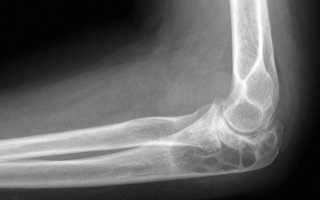

Фото артрита локтя: